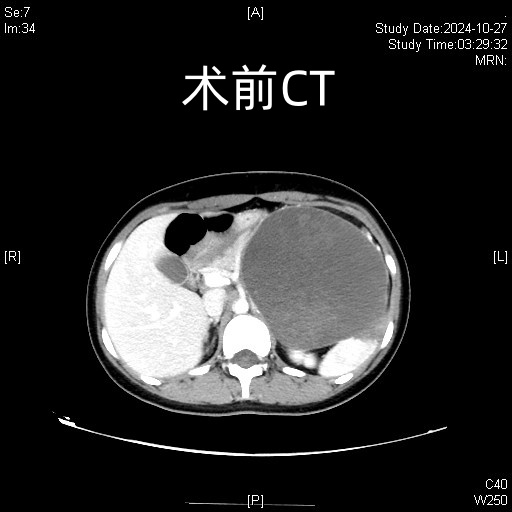

十八岁花样少女小赵(化名)跑步后突发左上腹痛,入院后经过仔细检查,发现胰体有一个约15cm*13cm的巨大肿瘤,考虑实性假乳状头状瘤,术前影像提示肿瘤与左肾、左肾上腺、左肾动静脉关系密切,侵犯脾动静脉,肿瘤压迫区域血管导致静脉严重曲张,手术难度大、术中出血风险极高,按照传统观念需要行开放胰体尾脾切除,左上腹会有一个长30cm大切口。

术前术后对比图